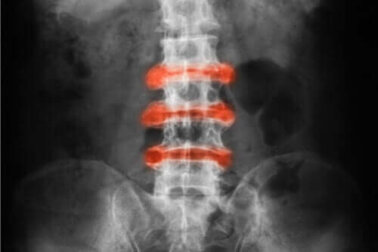

Morbus Bechterew ist eine entzündliche Arthritis, die hauptsächlich in den Gelenken des Rückens und des Beckens auftritt. Akute Beschwerden und Steifheit bessern sich in der Regel durch körperliche Aktivitäten, während Inaktivität die Krankheit verschlimmern kann.

- Morbus Bechterew (Spondyloarthritis): Eine entzündliche Arthritis, die hauptsächlich die Wirbelsäule betrifft.